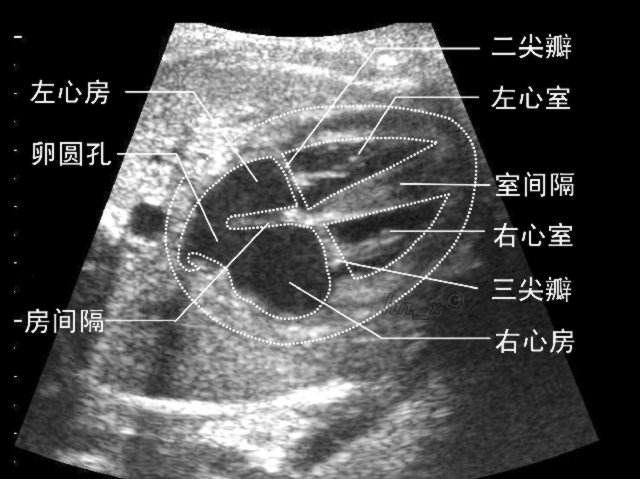

超声室诊断晚期妊娠胎儿心脏复杂畸形一例

4月中旬,超声室诊断并确诊一例晚期妊娠胎儿心脏复杂畸形,目前该女士已在我院终止妊娠。

张女士,怀孕39周,因常规孕检来我院做超声检查,超声医师对其进行常规项目检查后,发现胎儿心脏有异常。经进一步询问,该女士未行中孕期胎儿心脏超声检查,目前已错过最佳时期。超声医师反复仔细扫查后诊断为晚期妊娠胎儿心脏发育畸形(右室双出口、大动脉转位异常?室间隔缺损),经济南省级医院超声专家会诊后,最终证实我院超声诊断报告。张女士随后在我院终止妊娠。